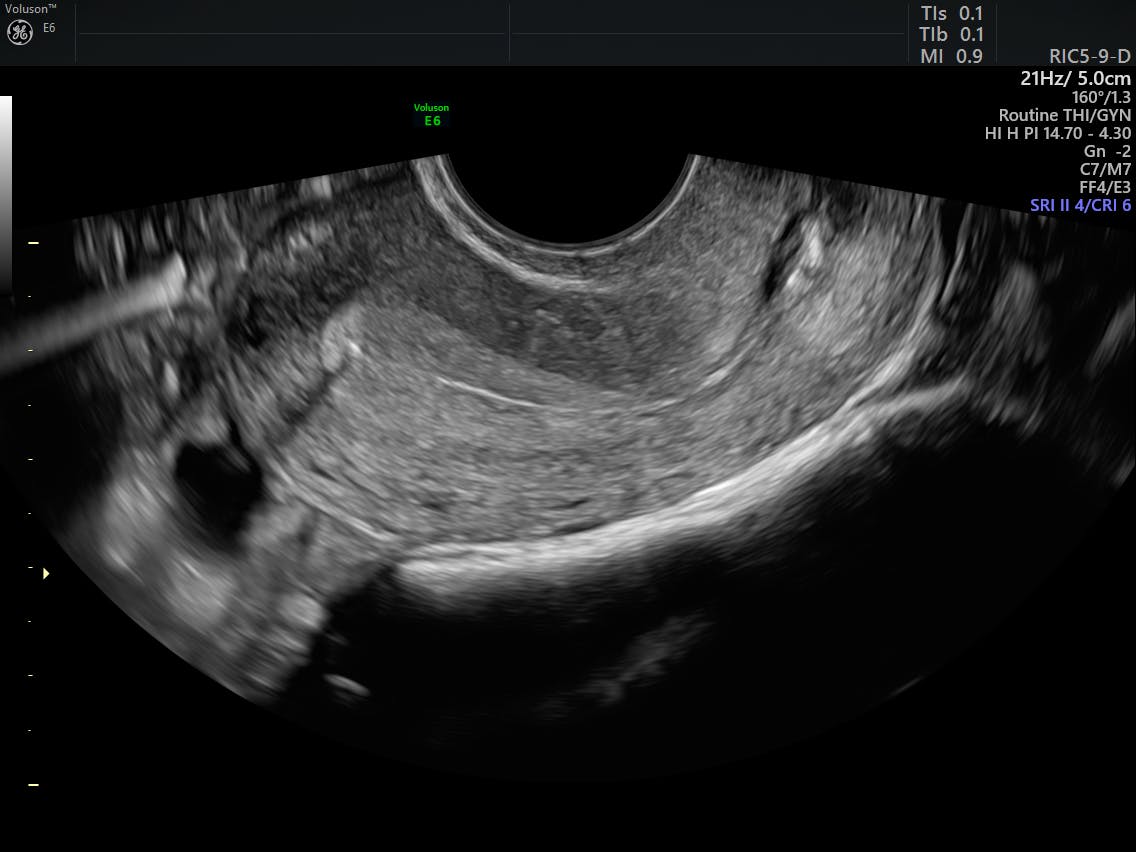

Post endometrial ablation syndrome. After an endometrial ablation women have varying severity and duration of cramps and vaginal discharge. Once healing of the uterine lining is complete most women experience lighter periods or even no periods. History and sonogram.

Recurrent tubal distention resulting from retrograde menstruation into occluded proximal fallopian tube segments by re. Any bleeding from persistent or regenerating endometrium behind the scar may be obstructed and cause problems such as central hematometra cornual hematometra postablation tubal sterilization syndrome retrograde menstruation and potential delay in the diagnosis of endometrial cancer. The most likely cause for this to occur is thought to be the presence of entrapped tissue or scarring that has occurred during the ablation procedure. Post tubal endometrial ablation syndrome is when there are loculated areas inside the uterus still menstruating but nowhere for the blood to go. It has been reported in 6-8 of these patients and occurs when bleeding from residual endometrium is obstructed due to surrounding uterine scarring and tubal occlusion 1. It causes monthly pain and on tv sonogrom should show blood trapped withing the uterusIf your tubes arent tied it could stil happen but is less lilkely. Ask your gynecologist if she preforms these. The post endometrial ablation syndrome is when the patients have to bear high degree of pelvic pain with or without a change in their bleeding pattern. Post endometrial ablation syndrome is a problem that women have after they have had a specific uterine treatment called endometrial ablation.